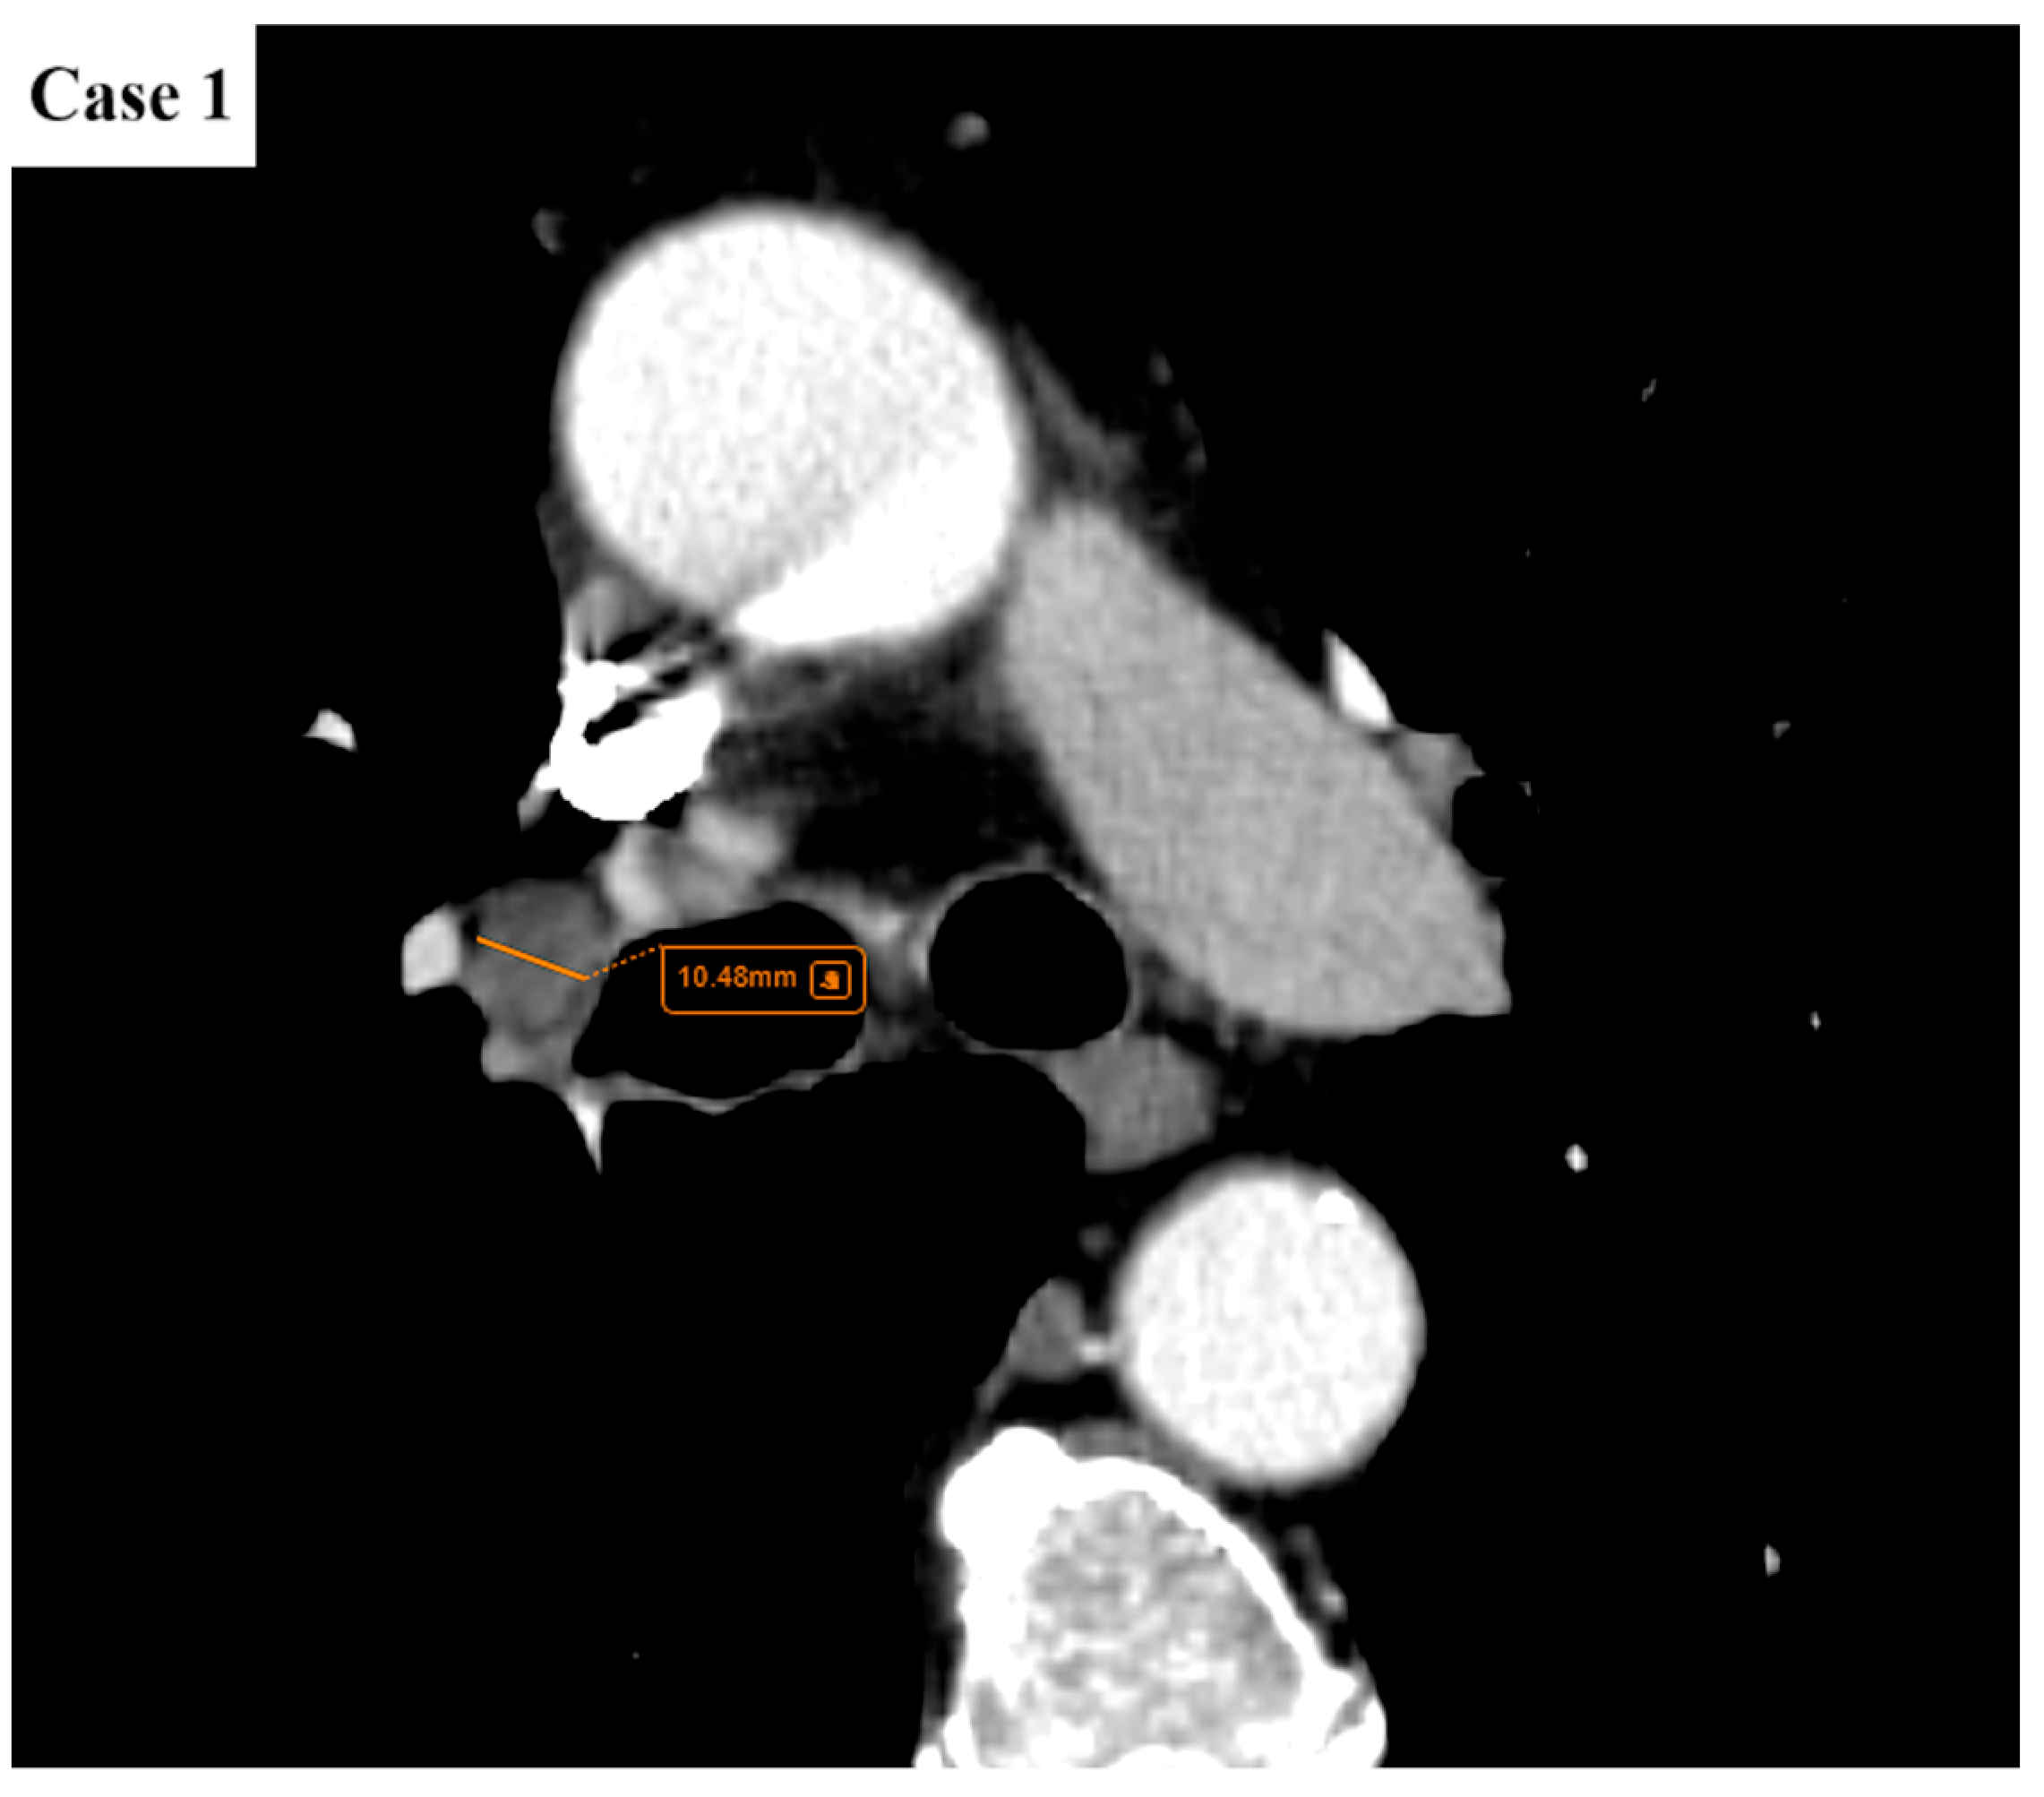

2.2. Data Collection and Imaging Evaluation

2.3. Staging Procedures